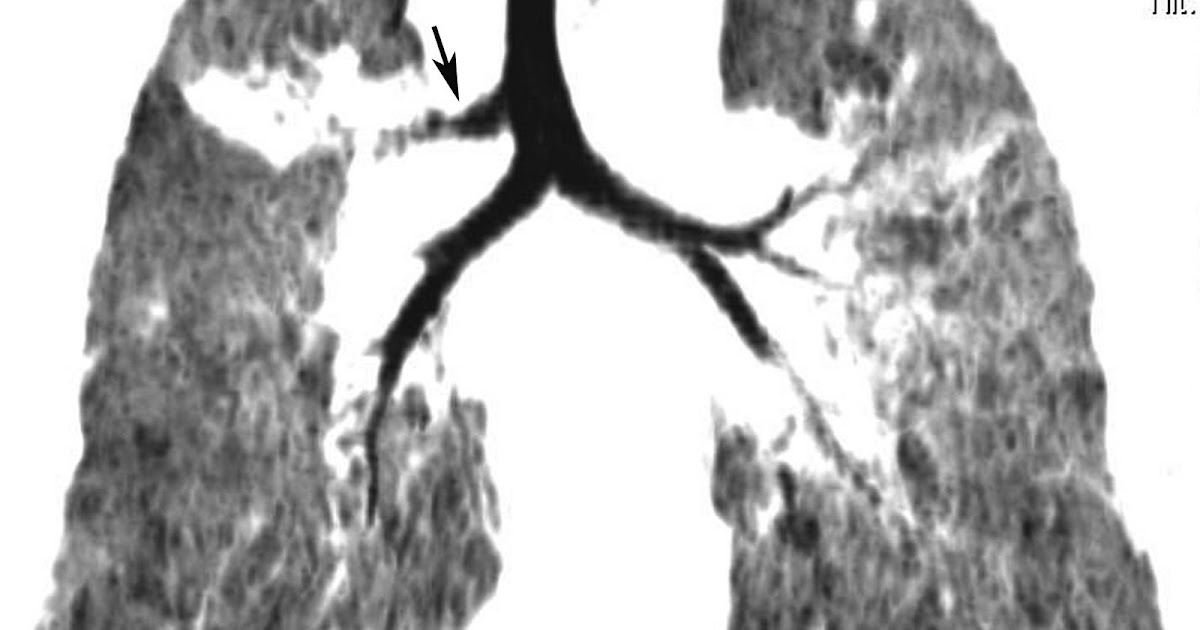

Aberrant bronchi to the upper lobes. Schematic shows prearterial (true

Tracheobronchial branching anomalies Coronal MPR showing a case of a Malformations Of Trachea And Bronchus Tracheal malformations consist of a variety of anomalies related to abnormal development of the tracheobronchial tree. Congenital malformations of the trachea, bronchi and lungs may produce bronchopulmonary problems of unusual and challenging clinical interest. In the first hours, days or weeks. Congenital anomalies of the chest are an important cause of morbidity in infants, children, and even adults. Congenital malformations. Malformations Of Trachea And Bronchus.